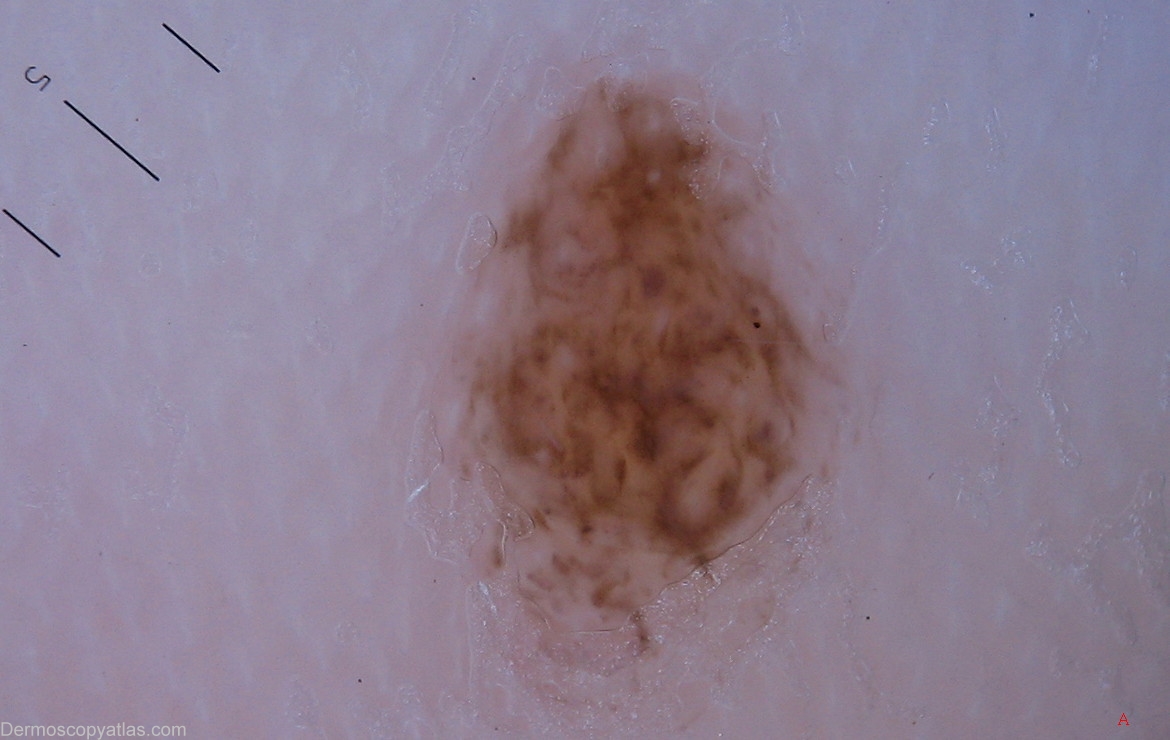

Diagnosis: Acral melanocytic naevus